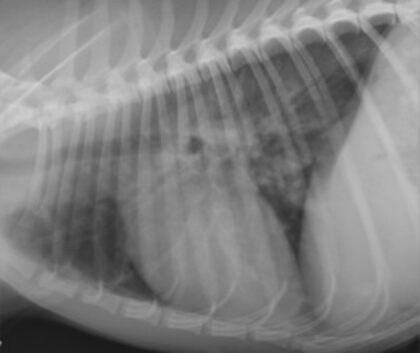

Die pulmonale Hypertension stellt ein extrem heterogenes Krankheitsbild mit vielen potentiellen Ursachen dar. Daher ist ein strukturierter Untersuchungsgang (Anamnese, Klinische Untersuchung, Röntgen, EKG, Echokardiographie, Laboruntersuchung), sowie das Wissen der Pathomechanismen, welche dann die Therapie bestimmen, absolut wesentlich. Die Einteilung kann in 5 Klassen oder einfacher in prä-, kapilär und postkapillär. In jedem Fall sollte eine Schweregradeinteilung wenn möglich erfolgen, um zu entscheiden ob eine Therapie notwendig ist. Die Medikamente die hierbei zum Einsatz kommen umfassen insbesondere die Phosphodiesterase 5 Hemmer wie das Sildenafil. Verlaufsuntersuchungen müssen dann zeigen wie die Therapie verändert bzw ausgedehnt werden muss. In diesem vetinar werden der strukturierte Untersuchungsgang, die Pathomechanismen und die Therapiemöglichkeiten der pulmonalen Hypertension beim Hund vorgestellt.